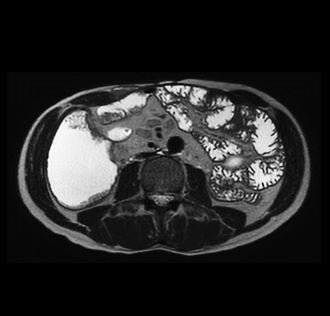

Beispiele von MRT-Dünndarm Aufnahmen

Die Hydro-MRT zeigt detaillierte Bilder des Dünndarms, insbesondere der Darmwand und der umgebenden Strukturen. So können entzündliche Veränderungen, Gewebeschäden, Abszesse, Fisteln und Verengungen frühzeitig erkannt werden.